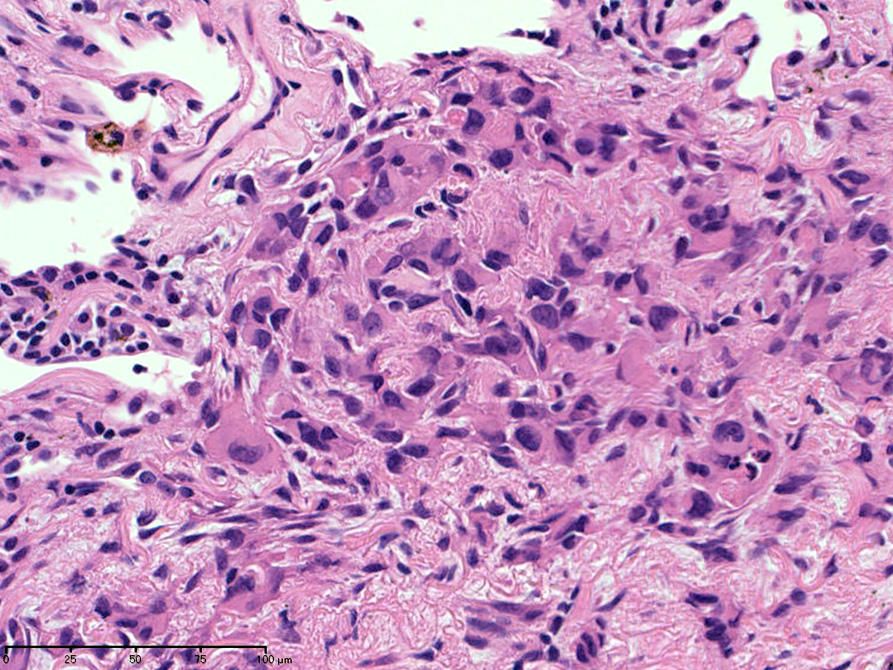

直径5-6mmの, 中央に弾性線維をふくむfibrous noduleがあり, 腫瘍細胞は結節の辺縁部に沿って認められる。

クリックすると大きな画像が見られます。